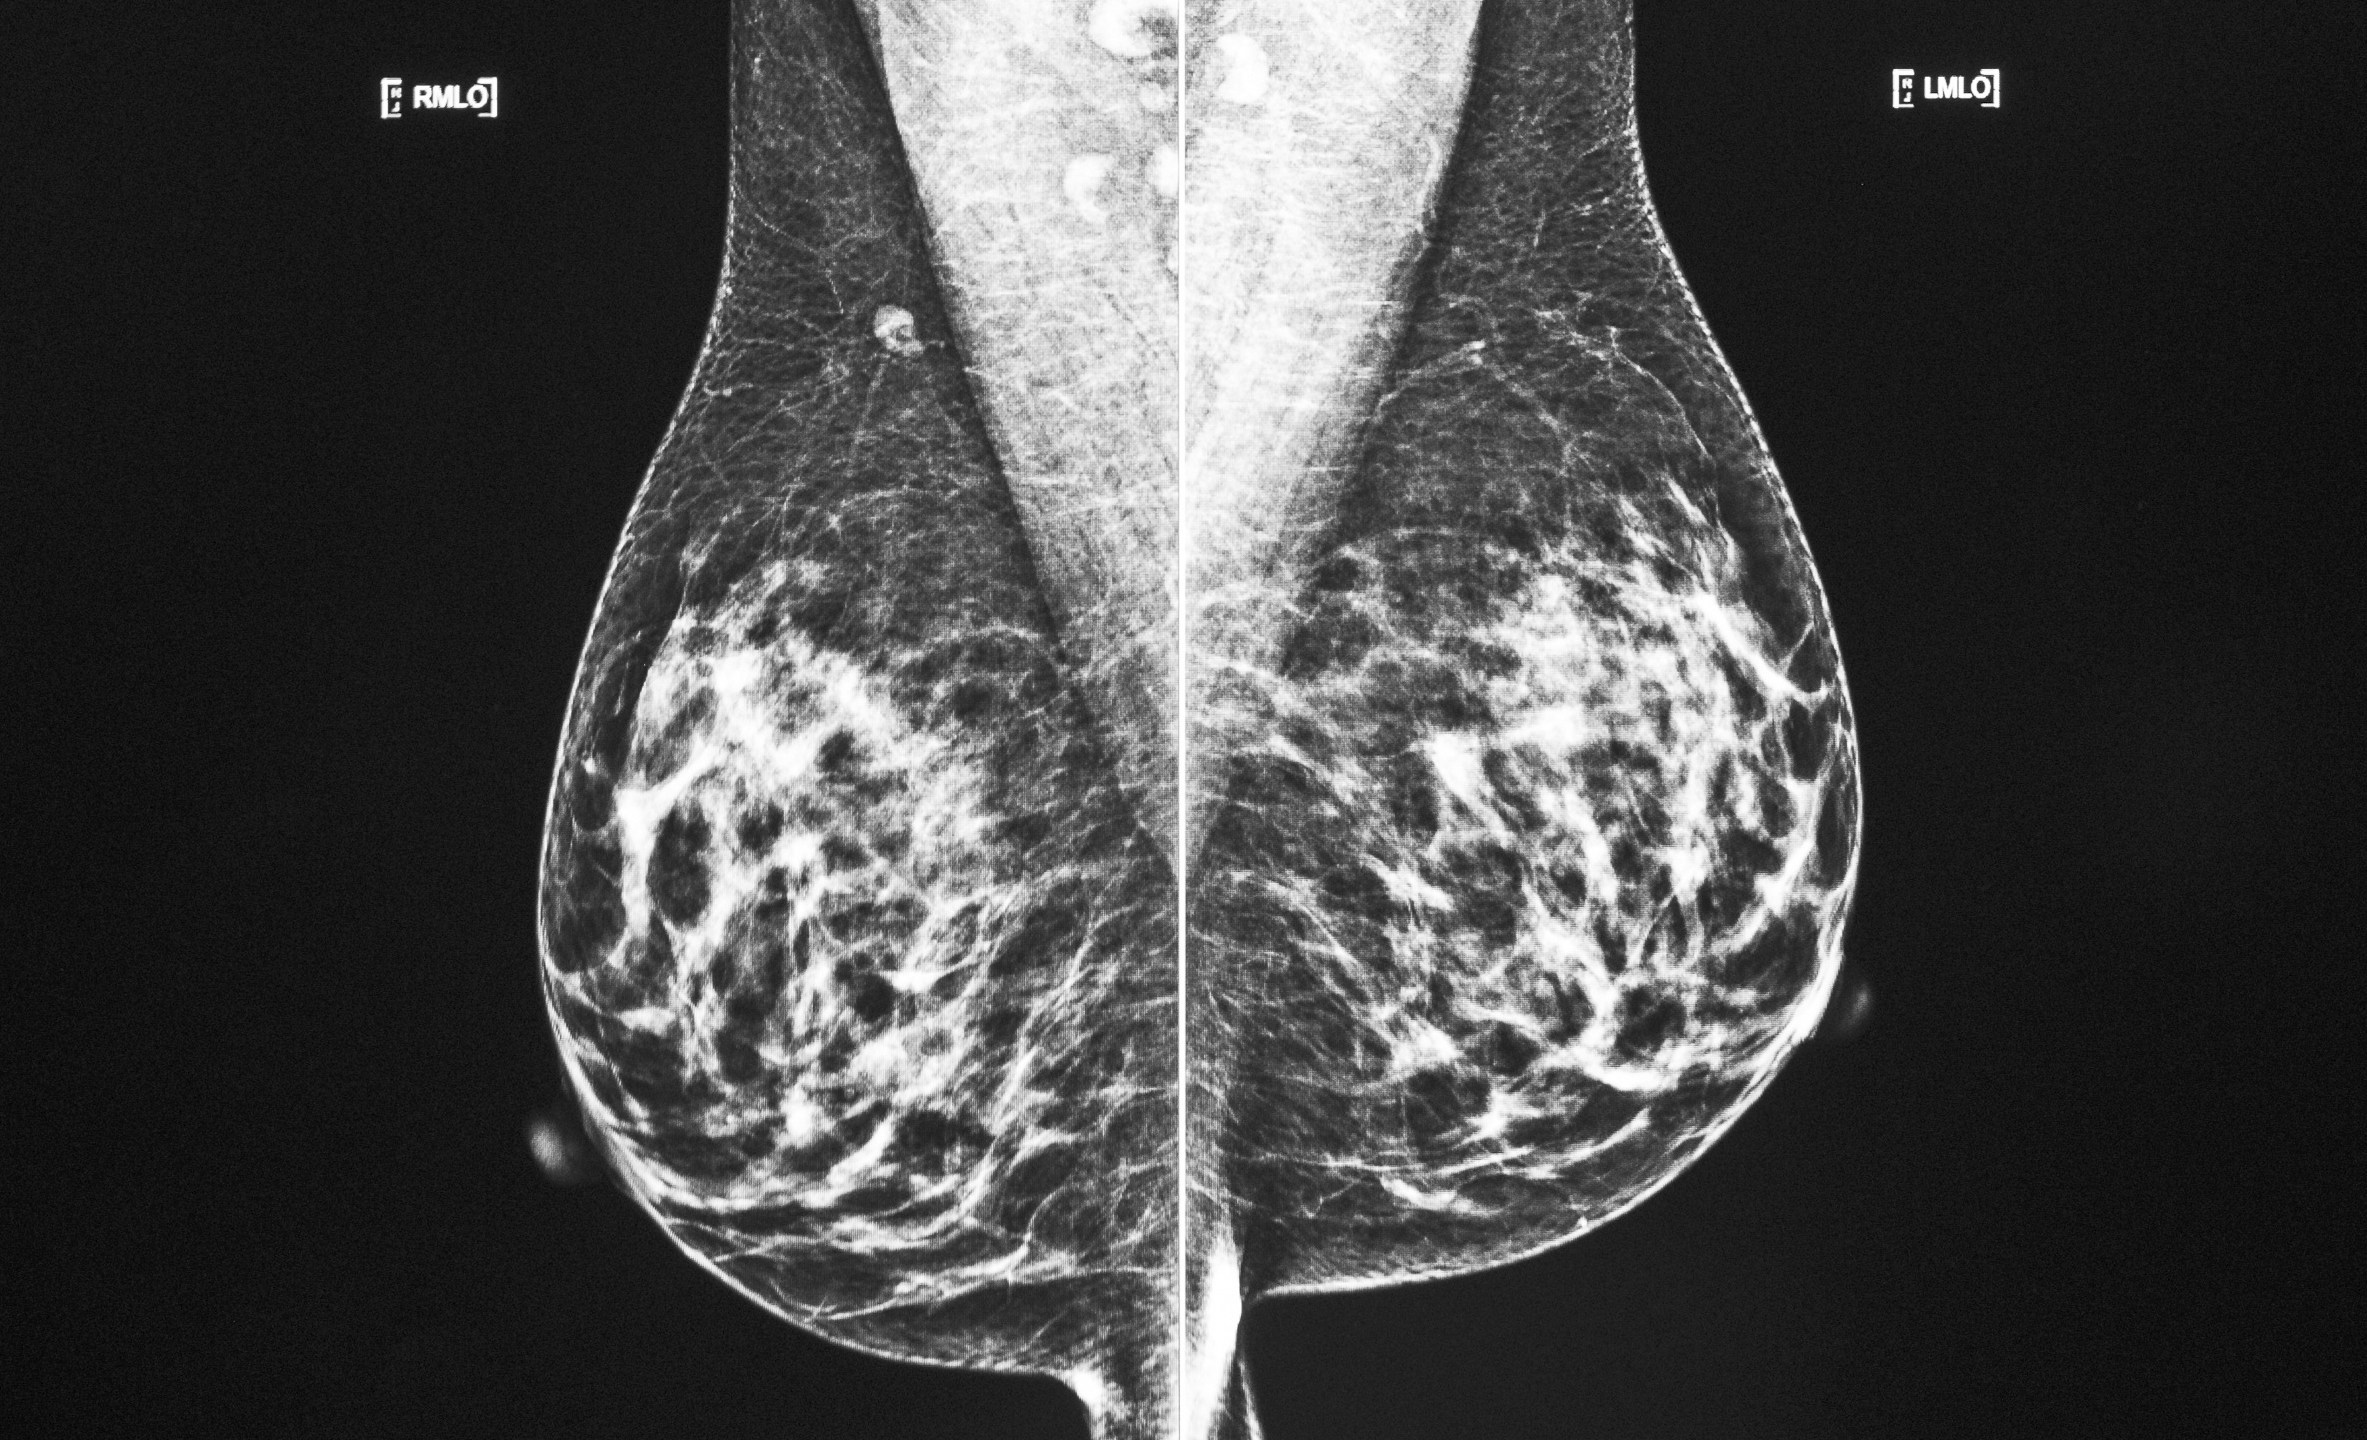

FILE – A technician displays images of a mammogram scan on a computer screen at a hospital in Odessa, Texas, on Wednesday, Oct. 20, 2021. A study discussed Friday, Dec. 9, 2022, at the San Antonio Breast Cancer Symposium finds many women with two or three breast tumors can get by with lumpectomy surgery instead of having their whole breast removed. (Eli Hartman|Odessa American via AP, File)